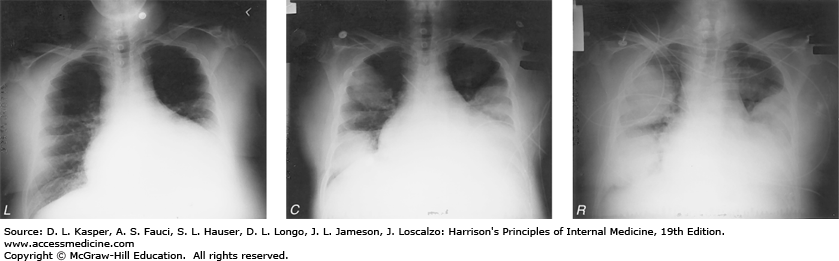

Legionnaires' Disease on Chest Radiograph

Chest radiographic findings in a 52-year-old man who presented with pneumonia subsequently diagnosed as Legionnaires’ disease. The patient was a cigarette smoker with chronic obstructive pulmonary disease and alcoholic cardiomyopathy; he had received glucocorticoids. Legionella pneumophila was identified by direct fluorescent antibody staining and culture of sputum. Left: Baseline chest radiograph showing long-standing cardiomegaly. Center: Admission chest radiograph showing new rounded opacities. Right: Chest radiograph taken 3 days after admission, during treatment with erythromycin.